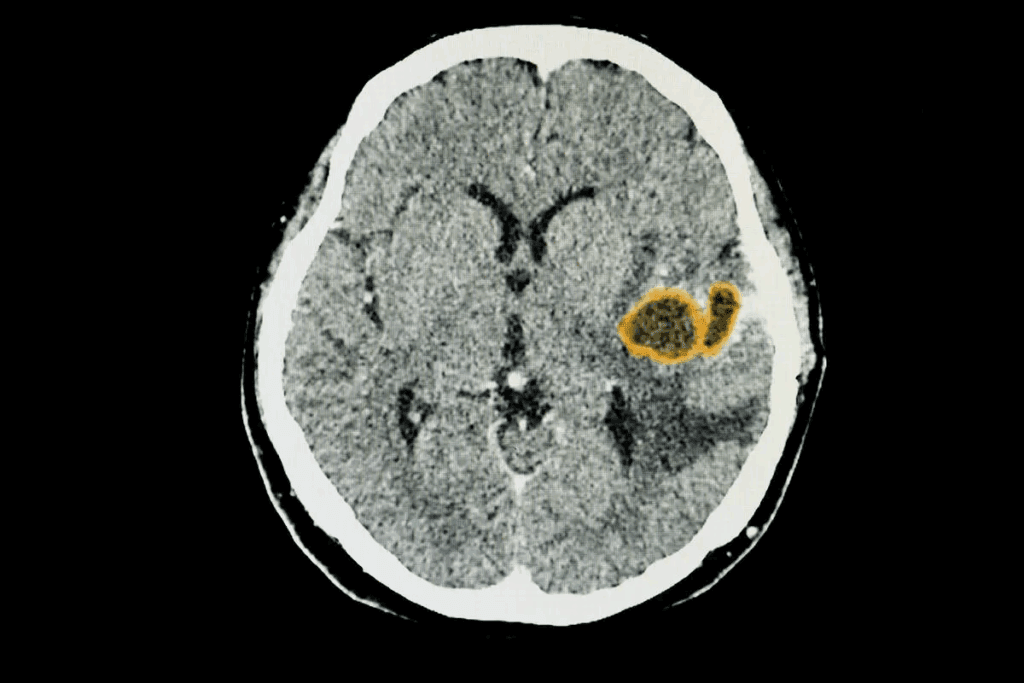

Ischemic Lesions

Ischemic lesions happen when a part of the brain doesn’t get enough blood. This is often due to a stroke or problems with blood vessels. These lesions can cause brain tissue to die and lead to neurological problems.

Imaging Techniques

Imaging techniques are vital for spotting brain lesions. The main ones are:

- Computed Tomography (CT) scans: CT scans give quick, detailed views of the brain. They help find lesions, bleeding, or other issues.

- Magnetic Resonance Imaging (MRI): MRI gives detailed images of the brain. It’s great for figuring out what kind of lesion it is, where it is, and how it affects the brain.